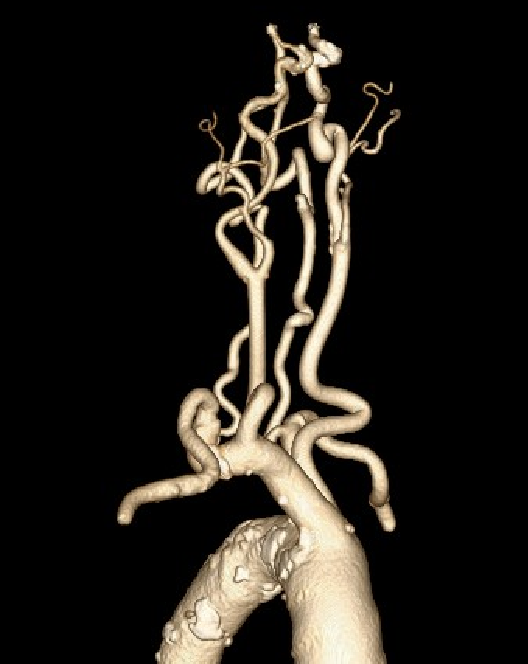

CTA提示右侧颈总动脉迂曲,右锁骨下动脉与右颈总动脉成钝角。